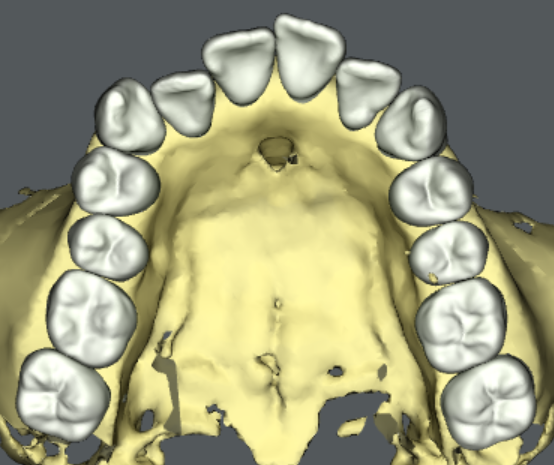

旭川公園通り矯正歯科では、問題点を解決するバーチャルセットアップを作成します。バーチャルセットアップとは、歯を動かす治療計画を三次元の仮想患者モデル上に再現したものです。個々の歯がどの経路を通ってどのくらい動くのかを視覚的に理解することができます。外科的矯正治療が必要な場合は、バーチャルオステオトミー(仮想患者モデル上での骨の移動)を行うこともあります。

当院で提供しうる治療方法と目標の全てを患者さんにご提示して、それぞれの利点と欠点、リスクとベネフィットをご説明します。患者さんには、バーチャルセットアップで可視化された治療目標を見ていただきながら、どの治療方法で矯正治療を開始するか共通認識のもとで決定していただきます。これが旭川公園通り矯正歯科で実施している「インフォームドチョイス」です。